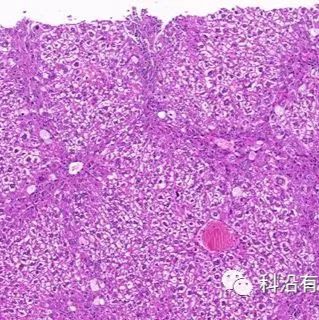

(三)主体内容:肝脏作为机体最为重要的代谢器官,炎症、毒性物质、肝脏感染(病毒、细菌、真菌、寄生虫等)都会导致肝脏损伤,影响机体的代谢活动。肝脏损伤后会发生自我修复,此过程伴随着纤维化的发生,病理性的肝脏纤维化是指肝脏在损伤后的修复过程中,胶原等细胞外基质的形成和降解平衡被破坏,导致肝脏内纤维组织过度积累。目前,中国是世界上的肝病大国。慢性肝病在其疾病进程中都会发生纤维化并朝着肝硬化、肝癌的方向发展,因此阻止肝脏纤维化,逆转纤维化是临床和药物科研过程中重要的一个选题。

3.实验结果鉴定:

大鼠肝纤维化模型